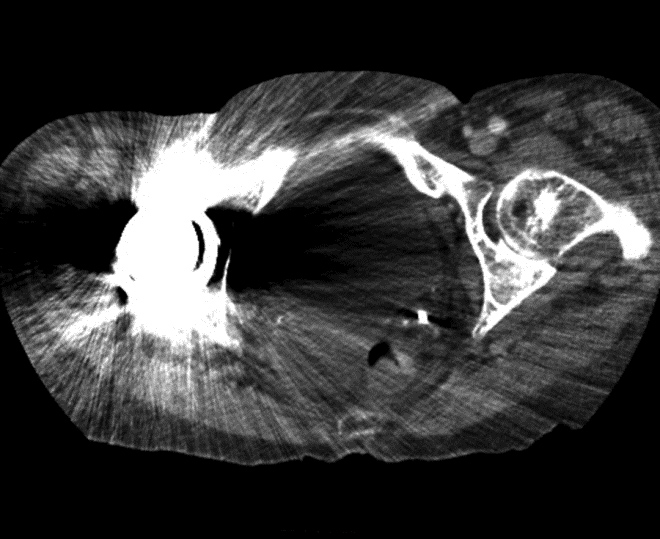

Bone (or “detail”) filters use a very sharp image filter, which accentuate fine spatial details, including image noise and artifact. Since musculoskeletal CT images are typically reviewed using “bone” windows (window 2000 HU, level 500 HU) these fine artifacts may be obscured and overlooked (Figure 4). In the presence of metallic hardware, these artifacts occur to a much greater extent and can result in degraded image quality. In the setting of metallic implants, it is helpful to use a soft image reconstruction, such as the standard filter used for general abdominal imaging, and even softer filters can be considered in the setting of highly attenuating implants, such as cobalt or steel, or if there is concern for soft tissue abnormality adjacent to hardware (Buckwalter, 2011). Evaluation of fine hardware in a small region of interest, such as a scaphoid fracture, offers an exception to this rule where a sharp bone algorithm may be beneficial (Ohashi, 2009).

Figure 3A Figure 3B Figure 4A Figure 4B

Artifact summation Artifact summation Windowing Windowing

Artifact Summation. (A) Scout image demonstrates bilateral total hip arthroplasties. (B) Axial CT image at the level of acetabular cup and femoral head shows severe transverse streaking related to total summed attenuation of metal components. Optimal Windowing. (A) Axial CT image of the pelvis viewed in soft tissue windows demonstrates extensive streak artifact due to total hip arthroplasty prohibiting evaluation of adjacent bone and soft tissue structure. (B) Same axial CT image set to bone windows results in improved visibility of adjacent bone and soft tissue anatomy.